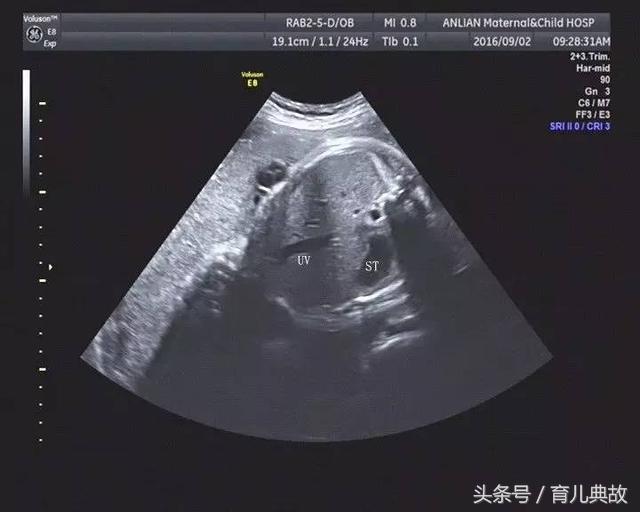

孕28周到了正常做超声检查的时间,原以为这次检查都会像以前一样平安度过,可是现实却把脸打的啪啪响,原来医生在检查时发现腹中宝宝没有胆囊,很可能是胆道闭锁。

无缘无故查出这种毛病,这消息对夫妻俩无疑是晴天霹雳。夫妻俩根本不相信会是这样的结果,可去了多加医院检查,可每次给出的答案都是如此:“没有显示胆囊,可能是胆道闭锁”。